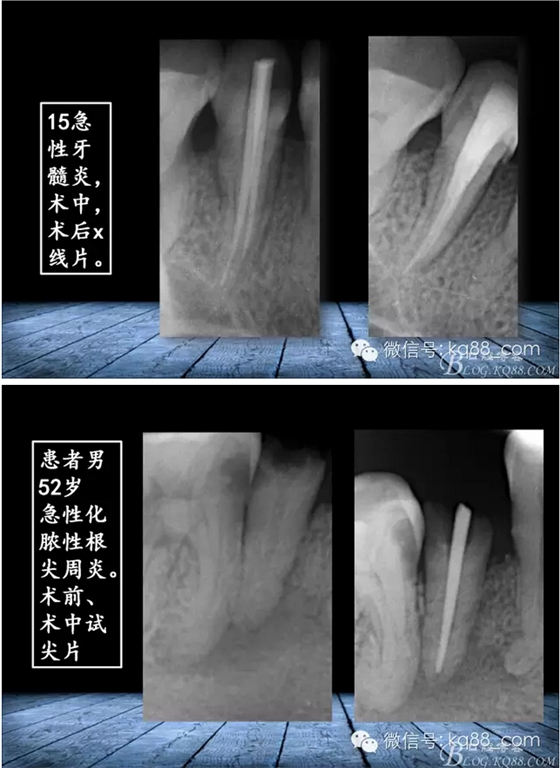

QQ圖片20150817140731.png

QQ圖片20150817140748.png